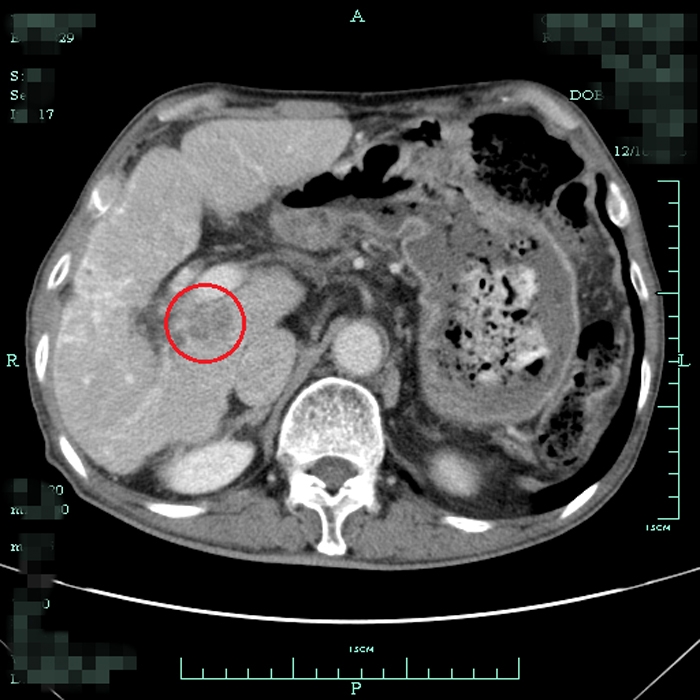

患者術(shù)前尾狀葉腫塊CT顯影

??? 一周前,73歲的毛大爺不幸被查出患上了“癌中之王”-肝癌。這一消息令全家人的心情異常沉重,更糟糕的是約2cm大小的腫瘤長在肝臟的尾狀葉。